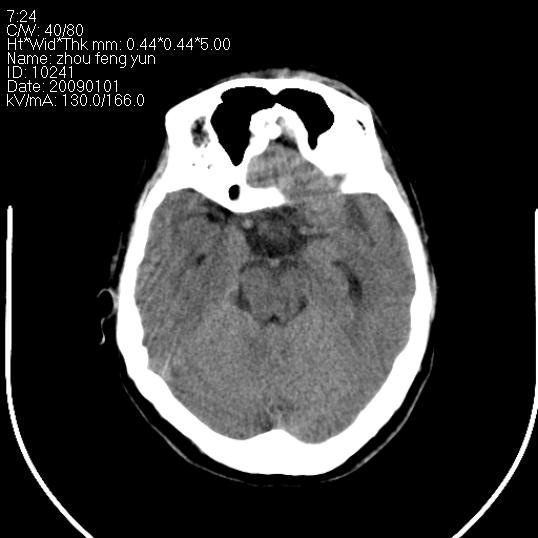

以下是引用hhcckk在2009-1-1 16:39:00的发言:[br]胼胝体嘴、膝部及部分体部发育不全,为囊状影替代,两侧侧脑室分离,脑室后角扩张[br][br]诊断:胼胝体发育不良[br][br]胼胝体发育不良(dysgenesis of the corpus callosum)是最常见的颅脑畸形,是胚胎期背部中线结构发育不良的一种形式。主要包括胼胝体缺如和部分缺如。胼胝体发育不良还可合并其他畸形,如胼胝体脂肪瘤、蛛网膜囊肿、脑膨出、chiari畸形、灰质异位症、脑回畸形等。[br][br]ct诊断要点:[br]1. ct横断扫描可见两侧侧脑室明显分离,脑室后角扩张,形成典型的蝙蝠翼状侧脑室外形。[br]2. 第三脑室扩大并向上插入两侧脑室体部之间,严重者第三脑室可上移到两侧大脑半球纵裂的顶部。在ct冠状扫描位显示更清。[br]4. 胼胝体畸形常伴有脂肪瘤,可测到其特征性脂肪密度。部分脂肪瘤的边缘可出现线样钙化[br]